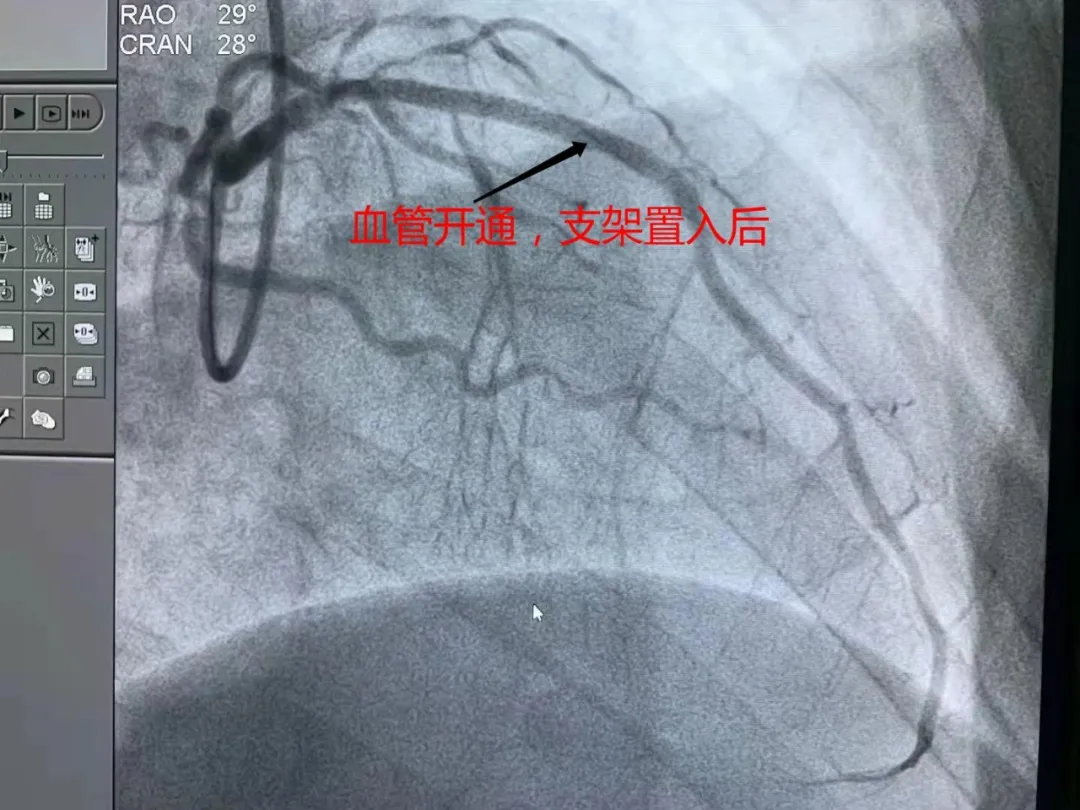

萬幸沒有發生意外,也好在血管閉塞的時間短。如果時間久了,不僅病人的愈後生活質量很差,再開通的成功率也很低。

這是非常粗大的前降支血管開通,支架置入後的影像。